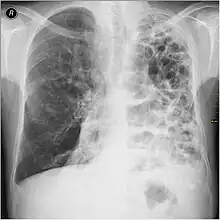

A chest X-ray and complete blood count may be useful to exclude other conditions at the time of diagnosis.[82] Characteristic signs on X-ray are hyperinflated lungs, a flattened diaphragm, increased retrosternal airspace, and bullae, while it can help exclude other lung diseases, such as pneumonia, pulmonary edema, or a pneumothorax.[83] A high-resolution CT scan of the chest may show the distribution of emphysema throughout the lungs and can also be useful to exclude other lung diseases.[25] Unless surgery is planned, however, this rarely affects management.[25] A saber-sheath trachea deformity may also be present.[84] An analysis of arterial blood is used to determine the need for oxygen; this is recommended in those with an FEV1 less than 35% predicted, those with a peripheral oxygen saturation less than 92%, and those with symptoms of congestive heart failure.[24] In areas of the world where alpha-1 antitrypsin deficiency is common, people with COPD (particularly those below the age of 45 and with emphysema affecting the lower parts of the lungs) should be considered for testing.[24]